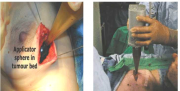

| 12:27, 3 במרץ 2015 | Irradiation4.png (קובץ) |  |

158 קילו־בייטים | Motyk | 1 | |

| 20:10, 2 במרץ 2015 | Irradiation3.png (קובץ) |  |

150 קילו־בייטים | Motyk | 1 | |

| 19:38, 2 במרץ 2015 | Irradiation2.png (קובץ) |  |

217 קילו־בייטים | Motyk | 1 | |

| 19:34, 2 במרץ 2015 | Irradiation1.png (קובץ) |  |

468 קילו־בייטים | Motyk | 1 | |